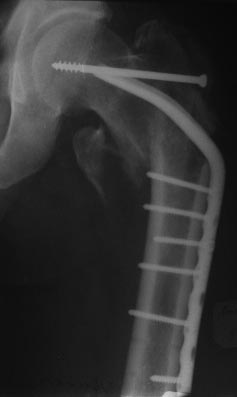

Имя     : 2 пРЕТБГИ?С 26.11.2012.jpg

Тип     : image/jpeg

Размер  : 21220 байтов

Описание: отсутствует

Url     : http://weborto.net:8080/pipermail/ortho/attachments/20130121/1122b3fc/attachment-0006.jpg